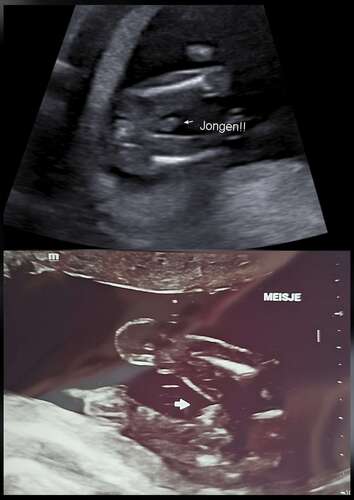

Goh, het lijkt inderdaad écht een jongetje op de echo van 16 weken! Dat ze het met 16 weken zelfs verkeerd kunnen zien!

hier met 15 weken echo gehad liet ze ook een piemeltje zien en zij ze een jongen 1 week later nog een echo gehad en toen zij ze ik kan toch echt niks meer zien het wordt een meisje😅 ik wacht nu gewoon af tot de 20 weken echo en hoop dan meer duidelijkheid te hebben. Ik heb al een zoontje en dochtertje dus wat het ook wordt met alle liefde welkom🥰

Ik had een geslachtsbepaling met 15+6 weken, ze gaf aan een meisje, maar deed er 35 minuten over om het te zien… paar dagen later zat ik bij de verloskundige en ik zei tegen haar dat is toch duidelijk een jongen of niet… zij twijfelde ook.

Heb met 17 weken nog een echo gedaan (ook zodat mn moeder een keertje mee kon om haar mee te laten genieten van de zwangerschap) en die gaf aan duidelijk een meisje.

oh nee. wat een omschakeling dan ineens. Dit is dus echt mijn grootste angst. Daarom wilde ik het bij de eerste niet weten. Nu heel sterk het gevoel gehad van een meisje. Bij geslacht echo (15+4) werd een jongentje gezien. Beetje zelfde foto als jou. Volgende week woensdag heb ik 20 weken echo. Daar gaan we het sowieso navragen. Daarnaast zijn de verloskundige heel duidelijk. Ik denk het zeker te weten, maar raad je wel aan tot 20 weken niks te kopen. 😅

Jaaaa hier ook. We hebben al een dochtertje en had echt een sterk voorgevoel voor een jongen. Het duurde even voor ze iets vond, want er zaten steeds 2 voetjes voor, hij zat in kleermakerszit 🤣 Maar het was idd vrij duidelijk, maar dat is de echo van TS ook!! 😵💫🤣 Nou moet ik zeggen dat die van ons wel echt zo'n vorm heeft van een balzakje en pieletje hahahaha maar toch... Ik ben ook vrijwel direct gaan shoppen...😬

nou echt hoor! Dat dacht ik dus ook. maar we kunnen iig gratis een nieuwe echo laten doen voor de geslachtsbepaling. Die vrouw snapt er ook niks van hoe dit heeft kunnen gebeuren. was haar nog nooit gebeurt in der hele carrière gaf ze aan 😂